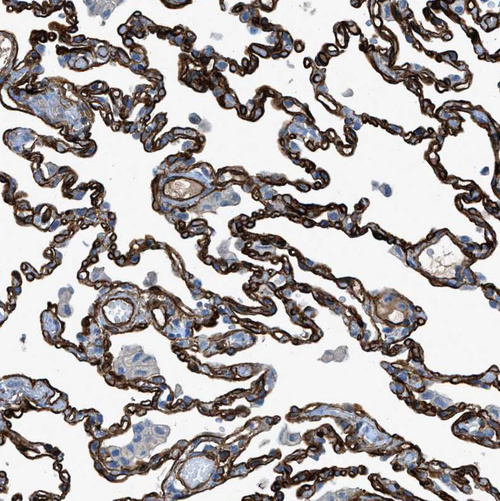

Immunohistochemical staining of human bone marrow shows strong cytoplasmic positivity in megakaryocytes.